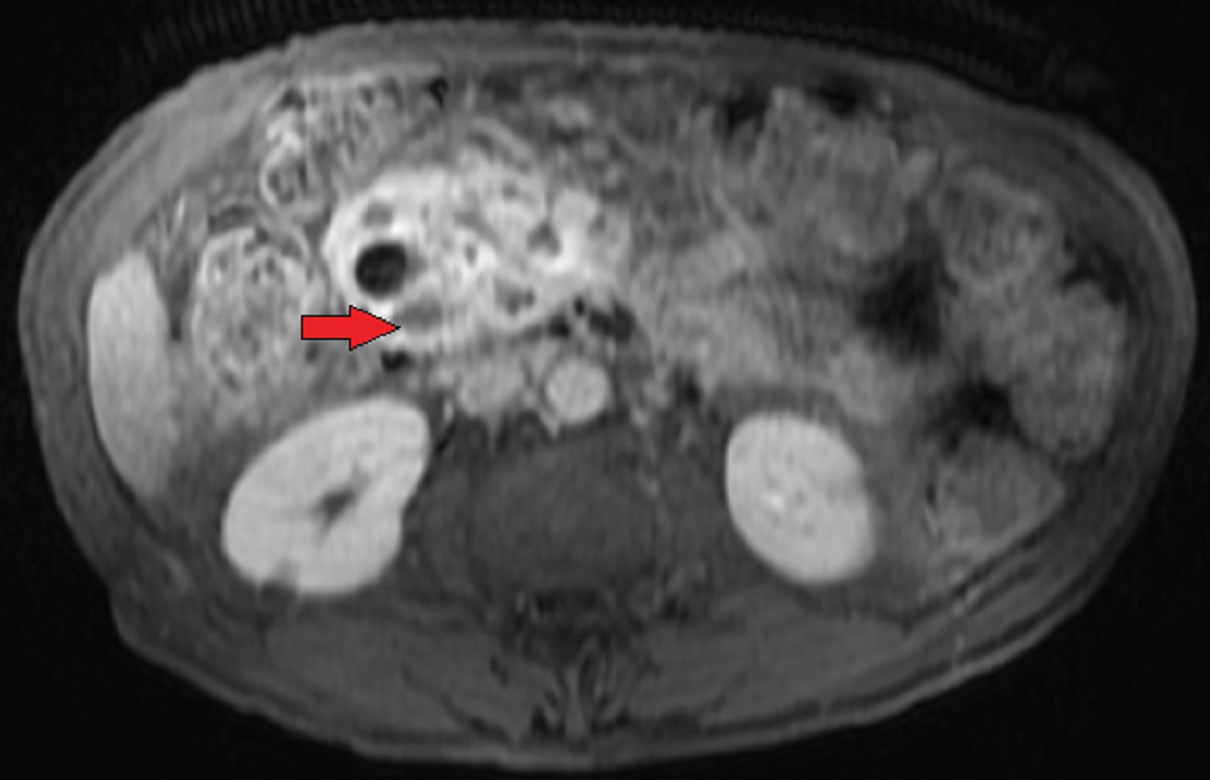

He was readmitted six months later with jaundice. CT scan [Table/Fig-1] was remarkable for a major dilation of the Wirsung duct associated to an enlargement of the main bile duct. MRCP [Table/Fig-2] showed enlargement of the pancreatic gland, multiple cystic lesions of the head of the pancreas with a major dilation of the main pancreatic duct. Intraductal hyperintense lesions were seen in the head, body and tail of the pancreas in the diffusion weighted images. There were no signs of liver or lung metastases. Endoscopic ultrasound with consideration for aspiration of cyst fluid was not done for logistical reasons. Lateral vision duodenoscopy failed to find mucinous output through the papilla. Carcinogenic embryonic antigen level was 5 UI/l. He was subsequently diagnosed with multifocal ITPN and underwent total pancreatectomy and splenectomy [Table/Fig-3].

Magnetic Resonance (MR) image showing enlargement of the pancreatic gland with multiple cystic lesions of the head (red arrow).